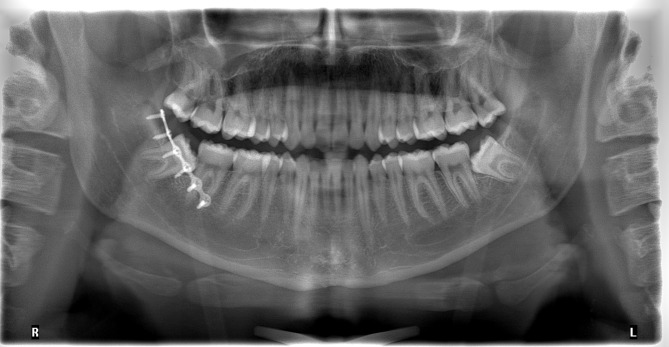

Methods: In this retrospective two-center cohort study, patients who underwent surgical treatment for mandibular angle fractures via a transoral approach using either 1-plate or 2-plate fixation over a 10-year period were included. Clinic A exclusively performed 1-plate fixation, while clinic B used 2-plate fixation. Demographic, clinical, radiological, and treatment data were analysed. Multivariable analyses were conducted to identify predictors of postoperative complications and secondary osteosynthesis.

Results: A total of 253 patients with 264 mandibular angle fractures were included. Violence was the most common mechanism of injury (n = 131; 49.6%). Postoperative complications occurred in 34.6% of the cases at clinic A and 26.8% at clinic B (p < 0.0001). Secondary osteosynthesis was required in 9.4% at clinic A and 7.6% of the cases at clinic B, respectively (p = 0.6547). Multinomial regression analysis identified smoking, diabetes mellitus, patient noncompliance, left-sided mandibular angle fractures, presence of a third molar (M3), partial M3 eruption, vertical depth A of M3 and horizontal impaction class II (Pell and Gregory) as significant predictors of postoperative complications. Logistic regression analysis identified smoking, diabetes mellitus, patient noncompliance, left mandibular angle fractures, mandibular angle und body fractures and presence of third molars as significant predictors of secondary osteosynthesis. As patient age there is an increased tendency for wound infection and plate/screw loosening (p = 0.06). A longer interval between trauma and surgery was associated with a higher risk of postoperative occlusal disturbances (p = 0.06). Patients with a longer duration of postoperative IMF were significantly associated with a higher rate of wound infection and secondary osteosynthesis (p < 0.05).